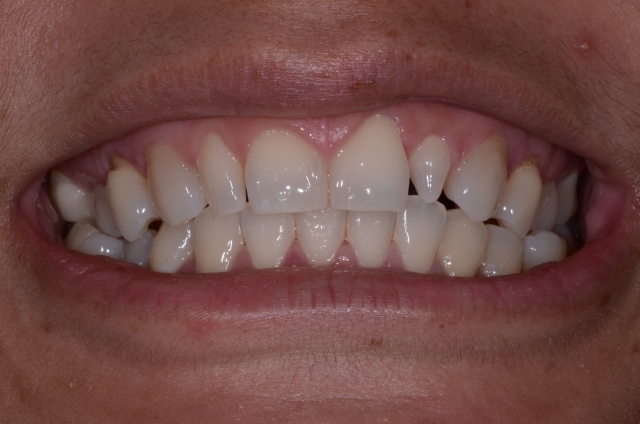

The first key to making this possible is that the teeth you’re dealing with must be smaller than the desired final size once they’re restored. This could be due to a genetic condition such as peg laterals (Fig. 1) or a case that involves excessive wear (Figs. 2–3).